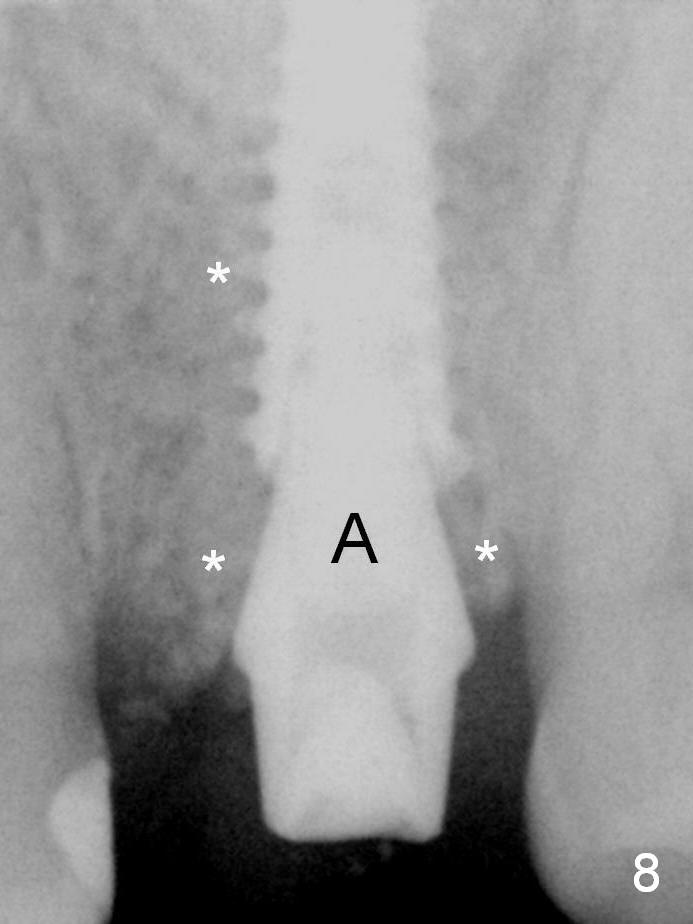

Continuously alternating use of MEs and drills leads to placement of a 5x11 mm implant with 30 Ncm insertion torque and sinus lift. After placement of bone graft (Fig.8 *) and 5x4(3) mm pair abutment (A), an immediate provisional is fabricated. Fig.9 is a PA taken higher than Fig.8 to show the sinus floor and the mesial wall of the socket (red dashed line).